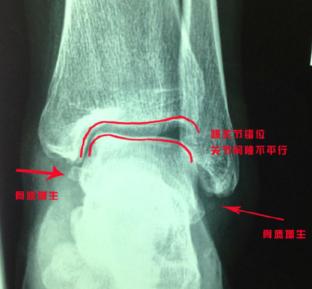

首先对脚踝进行了距骨前移、腓骨下移与跟骨内翻手法的复位。

那是因为损伤的韧带没有完全修复,踝关节一直处于不稳定的状态,踝关节为了增加稳定性产生了肌肉代偿。久而久之,足踝肌肉常常会产生疲劳感,这会使踝关节更加不稳,出现“习惯性扭脚”。长此以往,关节会出现错位和骨质增生。